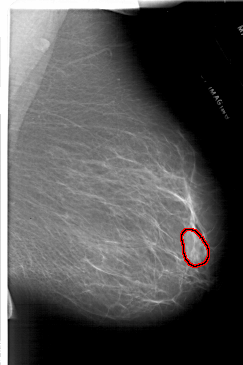

FILE: A_1717_1.RIGHT_MLO.OVERLAY

TOTAL_ABNORMALITIES 1

ABNORMALITY 1

LESION_TYPE MASS SHAPE LOBULATED MARGINS ILL_DEFINED

ASSESSMENT 4

SUBTLETY 3

PATHOLOGY BENIGN

TOTAL_OUTLINES 1

BOUNDARY